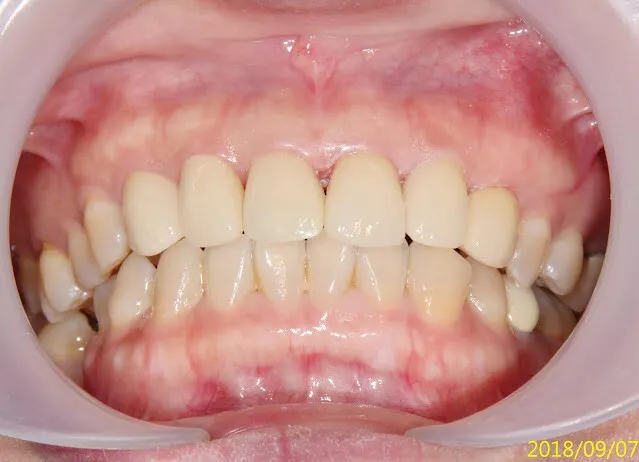

請注意開始是2017,花了一年多,才終於走到裝正式假牙

再經過一年,假牙看起來更自然了,當初剛裝假牙時的牙齦,病人自己說大概一個多月就自動長好恢復了

正中門牙的黑三角,無解,那是成人重做門牙或矯正常見的問題,因為已不像年輕人的牙齦那麼有再生活力與適應力,所以很多牙醫師都喜歡做連在一起的假牙,解決黑三角的問題(可參考她最上面的原始假牙),可這是對醫師方便、好,對病人的健康並不好。